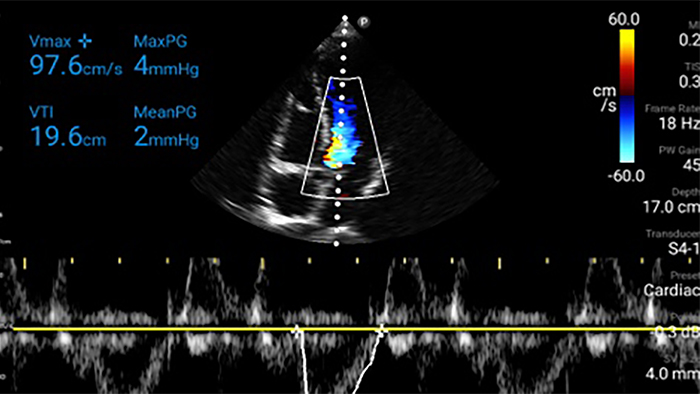

Every second counts in cardiac care

Heart attack patients need immediate care. Lumify's cardiac presets can help patients get diagnosed faster to improve their outcomes.

• 4 to 1 MHz extended operating frequency range • 2D, color Doppler, M-mode, advanced XRES and multivariate harmonic imaging • High-resolution imaging for abdominal and cardiac applications: Cardiac, OB/GYN, Lung, Abdomen and FAST imaging preset optimizations Lumify aids life-saving technology in prehospital setting